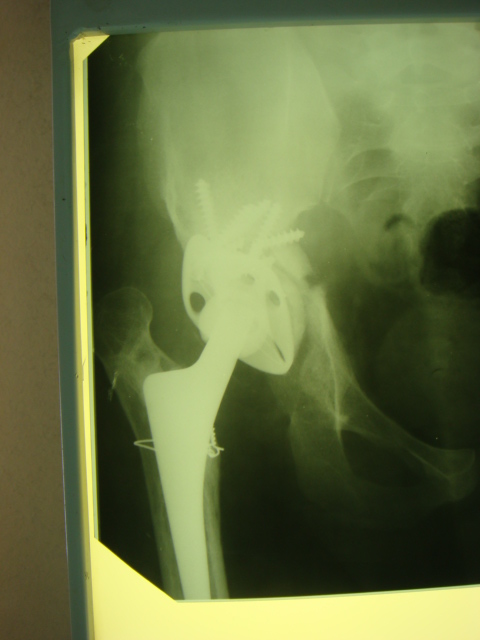

Обращение в нашу клинику в 2008 г. - демонтаж аппарата (рис. 4). Сегодня укорочение 8 см. Слева - протез стабилен, безболезнен.

Что делать дальше?

1. ревизионное ЭП правого ТБС?

2. формирование опорного бедра?

3. Удлинение бедра на АВФ?